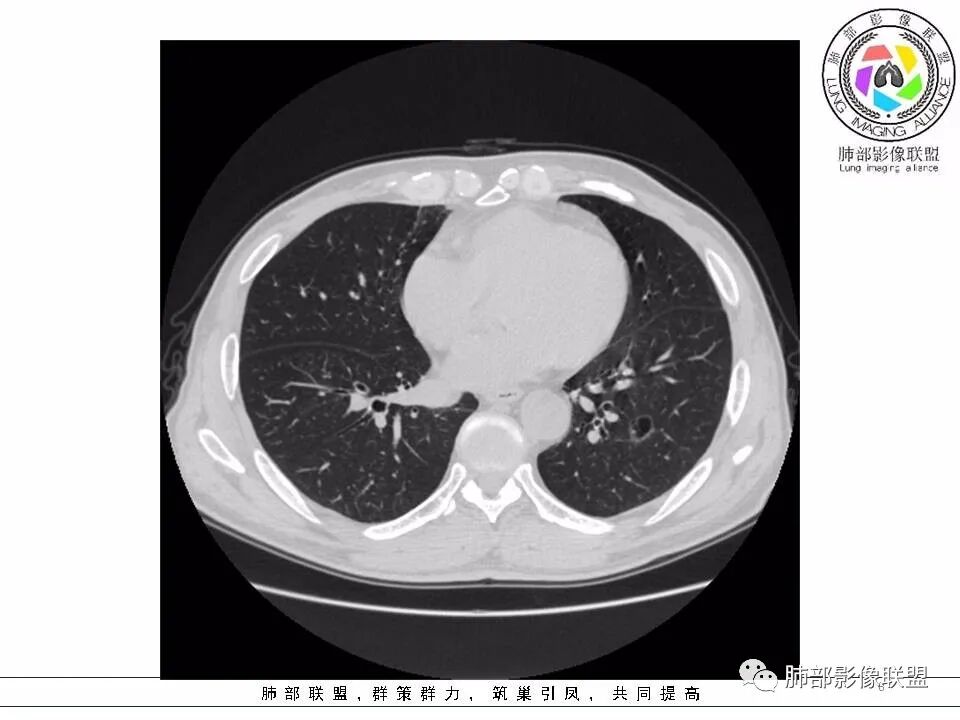

【每日晨读】黄色预警--警惕囊腔型的病变

左肺下叶囊腔,壁厚薄不均,可见磨玻璃成分!考虑恶性可能,腺癌?

左下肺囊性病变,边界不规则,有磨玻璃,内分隔,壁厚薄不均,内有壁结节,考虑囊腔样腺癌。

男性,发热,肿瘤标志物不高,影像:左下肺类圆形囊腔,内有丝丝缕缕,周边有渗出,右肺少许条索,第一印象:囊腔型腺癌

老年男性,左肺下叶囊腔,与临近支气管关系紧密,壁厚薄不均,周围可见实性成分,腔内密度不均匀,可见索条及结节,考虑囊腔型肺癌

男性患者,左肺下叶囊性病变,壁厚薄不均,部分壁较厚,周围可见磨玻璃影,考虑周围型肺癌,腺癌可能。

左下肺囊性病变,边界不规则,周围见磨玻璃影,内分隔,壁厚薄不均,考虑囊腔样腺癌可能性大,鉴别肺大泡合并感染,首次发现建议至少复查一次看看。

中年男性,发热伴咳少量白痰,左下肺可见一囊性空腔,壁厚薄不均,局部周围GGO,边界较清,内见分隔及结节,常规考虑囊腔性腺癌

间断发热半月余。半月前无明显诱因出现发热,体温波动于38℃,畏寒,轻咳,少量白痰,时有活动后胸闷气喘。无胸痛、心慌、乏力、盗汗、消瘦、咯血。于当地诊所予以头孢静脉输注一周,体温正常3天后再次出现体温升高。波动于37.2℃。实验室检查没有太多的问题。左肺下叶囊腔病变,壁比较薄,部分环壁局限性的增厚,边界毛糙,略显模糊,并见与支气管相连,未见明显的壁结节,而囊壁内见丝丝缕缕的索状影。考虑良性病变,毛霉菌感染或隐形性感染,鉴别寄生虫肺部感染。

2.左肺下叶外基底段囊腔样病灶,轮廓柔和,壁厚薄不均,见壁结节。内见分隔或脊状突起。腔内见血管穿行。

这是有“故事”的囊!

3.囊壁外环以磨玻璃影,边界较清楚。

1.囊腔壁厚薄不均,壁结节,内有分隔,其内有血管穿行,指向新生物。

2.临近有边界清楚磨玻璃影,指向腺癌。